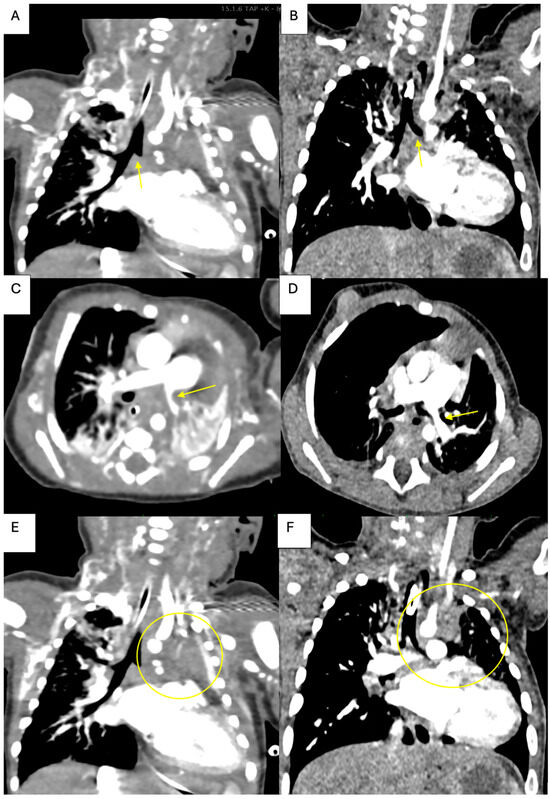

2. Case Presentation